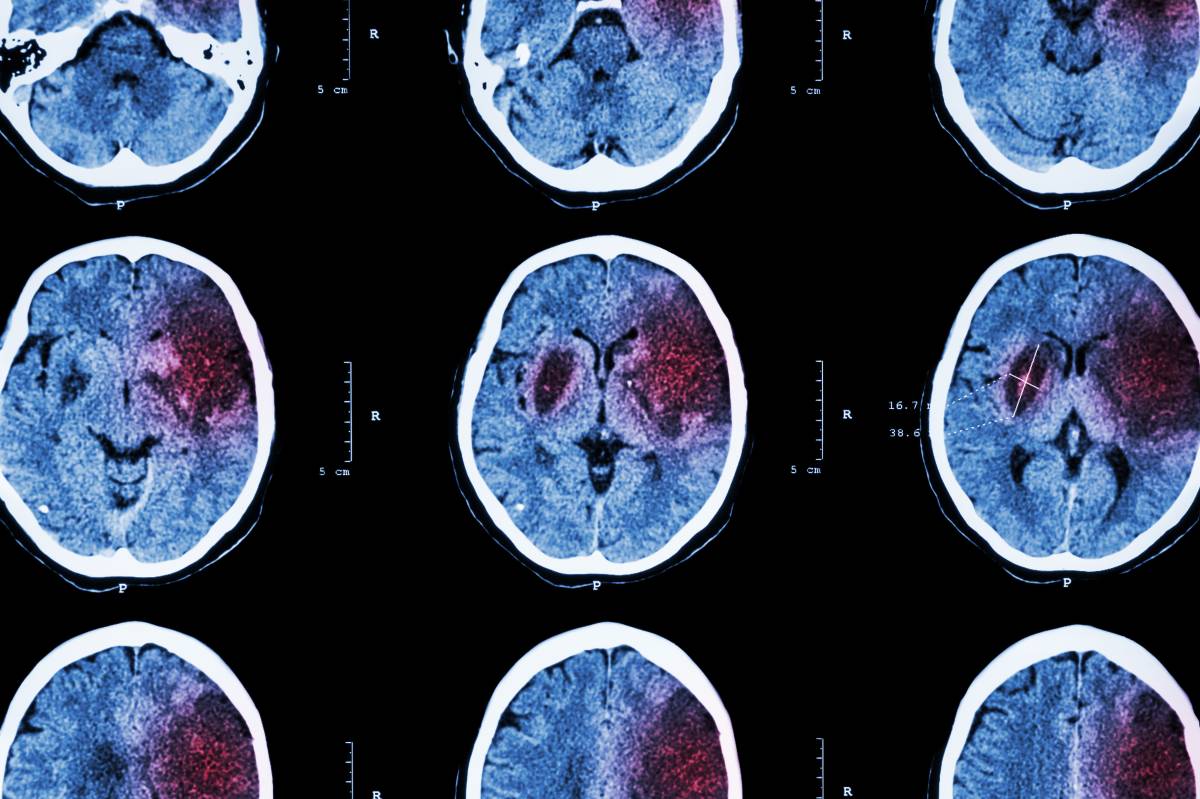

2021-10-11 15:57:00众所周知,中风患者早期进行康复治疗,可以促进受损的大脑功能恢复,防止并发症进一步恶化,为日后恢复正常的工作与生活做好相应的准备。

临床上,作业治疗主要适用于各种原因引起的肩关节活动受限,关节周围肌力减退,关节粘连、挛缩的关节锻炼。据统计,中风患者85%有上肢运动功能障碍。他们非常适合采取作业治疗来促进上肢功能康复。